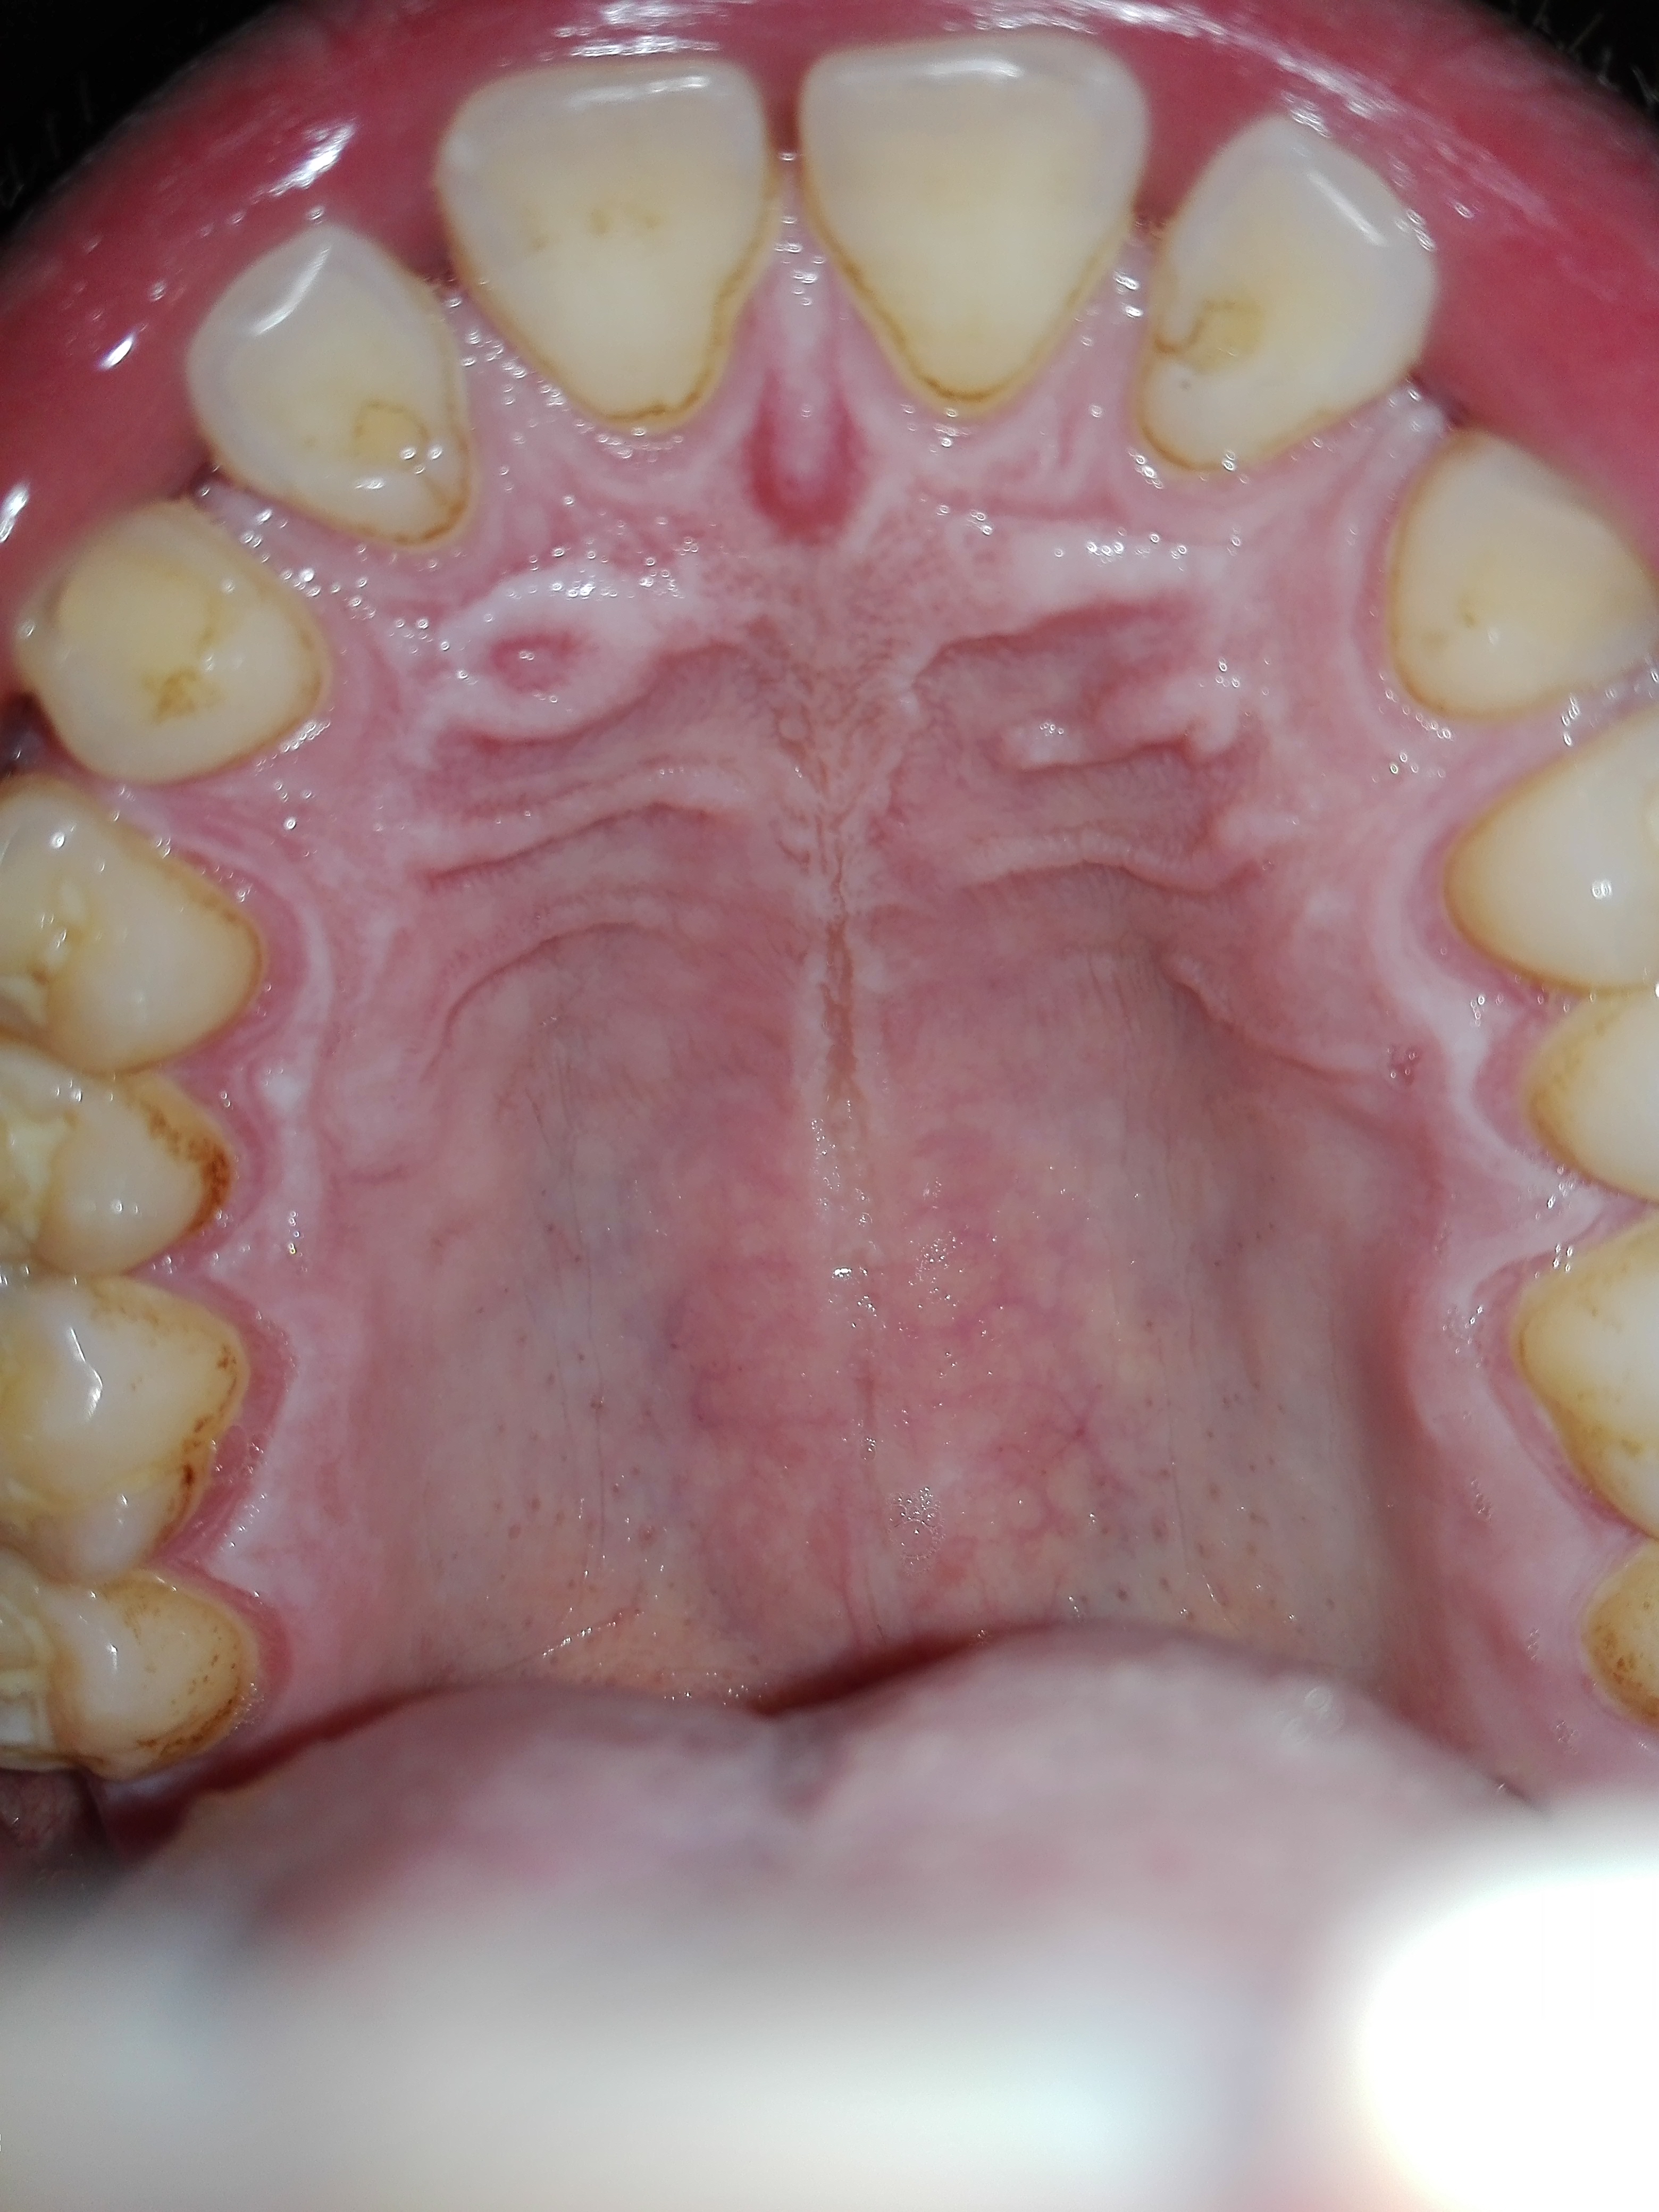

Questa bollicina può essere una conseguenza della forte infezione che ho avuto?

Buongiorno, vi scrivo perché vorrei un consiglio. Il giorno venerdì 31 marzo ho iniziato un ciclo da 6 giorni di Augmentin e ho finito di prendere l'ultima pastiglia giovedì 6 aprile mattina. L'antibiotico mi é stato prescritto dal dentista dato che il dente del giudizio inferiore sinistro stava spuntando e mi causava forte dolore, gonfiore,